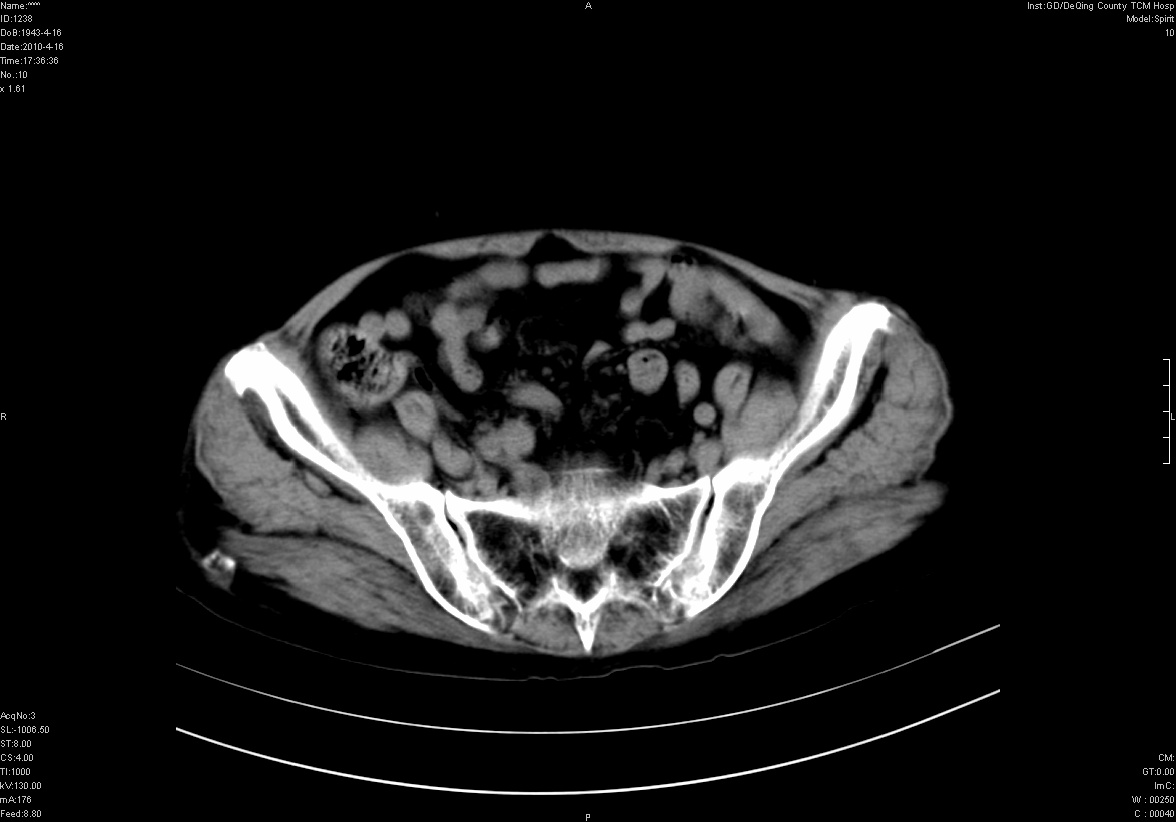

标题: CT25796:女,60岁,腹痛5天,请会诊??? [打印本页]

标题: CT25796:女,60岁,腹痛5天,请会诊???

考虑卵巢畸胎瘤。

支持右侧盆腔畸胎瘤。

右侧附件畸胎瘤

考虑右侧卵巢畸胎瘤。

考虑右侧卵巢畸胎瘤

右侧卵巢畸胎瘤可能。